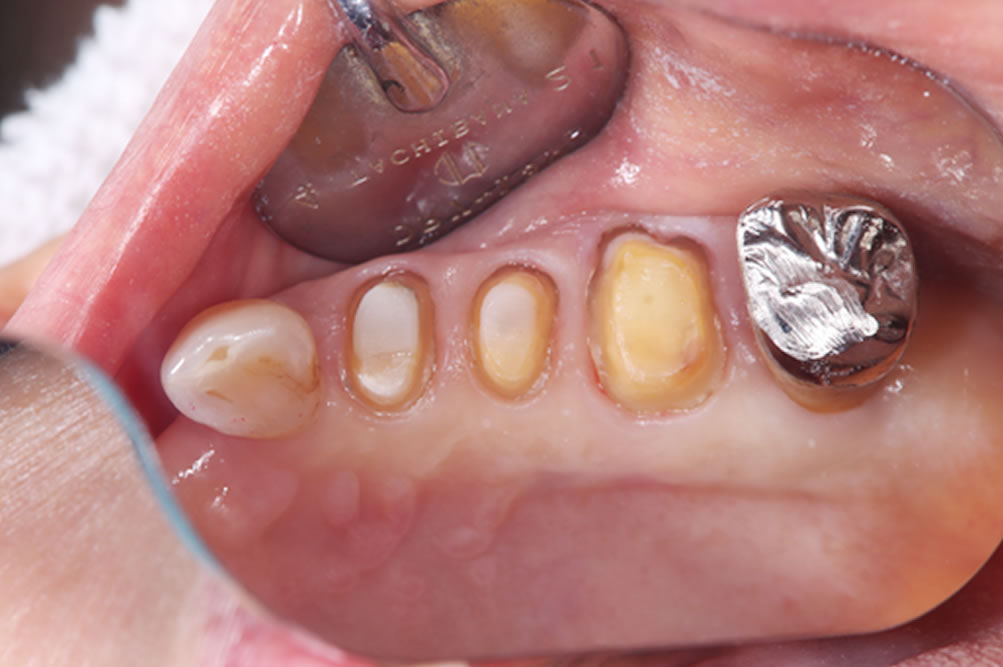

- 11.13 ②銀歯の除去

- 11.14 ③虫歯の除去

- 11.15 ④支台形成

プロビジョナル(精密仮歯)装着

【下顎】

下顎に埋入したインプラントにプロビジョナル(精密仮歯)装着しました。

【上顎】